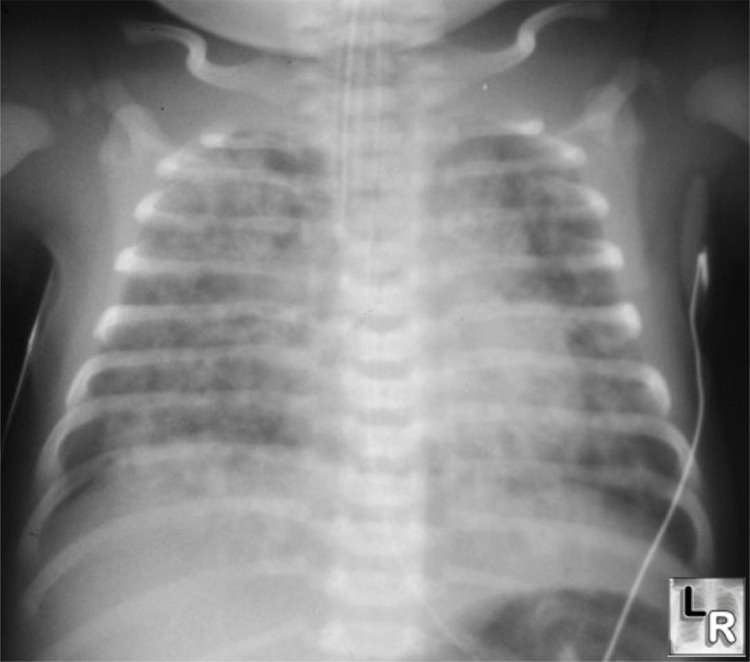

يتم تشخيص متلازمة استنشاق العقي لدى حديث الولادة من خلال الأعراض و العلامات , و يؤكد التشخيص بوجود العقي في الرغامى أو السائل الأمنيوسي بالإضافة إلى وجود أعراض الضائقة التنفسية و موجودات صورة الصدر التي تظهر نمط الارتشاحات المنتشرة مع فرط الانتفاخ .

يتطور استرواح الصدر (الريح الصدرية ) عند 10% من الرضع الذين لديهم متلازمة استنشاق العقي .